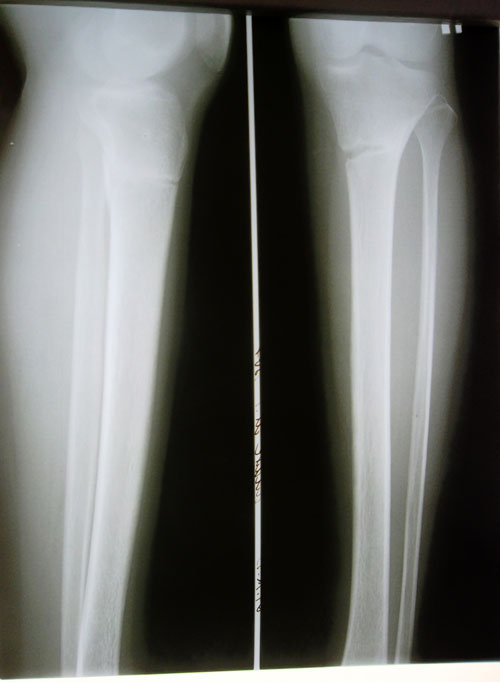

Дата операции 03.07.2013г.

Дата снятия аппаратов 15.10.2013г.

Срок лечения 103 дня.

Рентген в 2 месяца после снятия аппаратов.

Рекомендовано: ещё месяц воздержаться от ношения каблуков. Через месяц начните с 5-6 см, постепенно по нарастающей (я про каблучки). Можете посещать занятия боди балетом для растяжки и красивой осанки и походки(это можно делать в домашних условиях по интернету). Ждём фото ножек на каблучках! Не забывайте про форум!